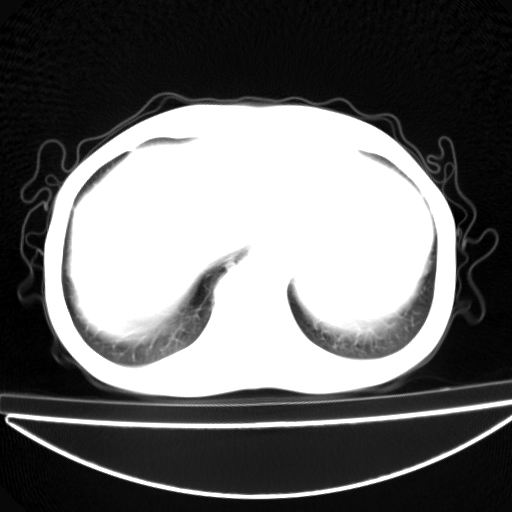

以下是引用杀毒软件在2009-4-28 17:58:00的发言:[br]考虑----左肺慢性肺脓肿形成继发上叶含气不良---抗炎后复查---待排肿瘤所致[br][br][本贴已被 杀毒软件 于 2009-4-28 18:01:26 修改过]